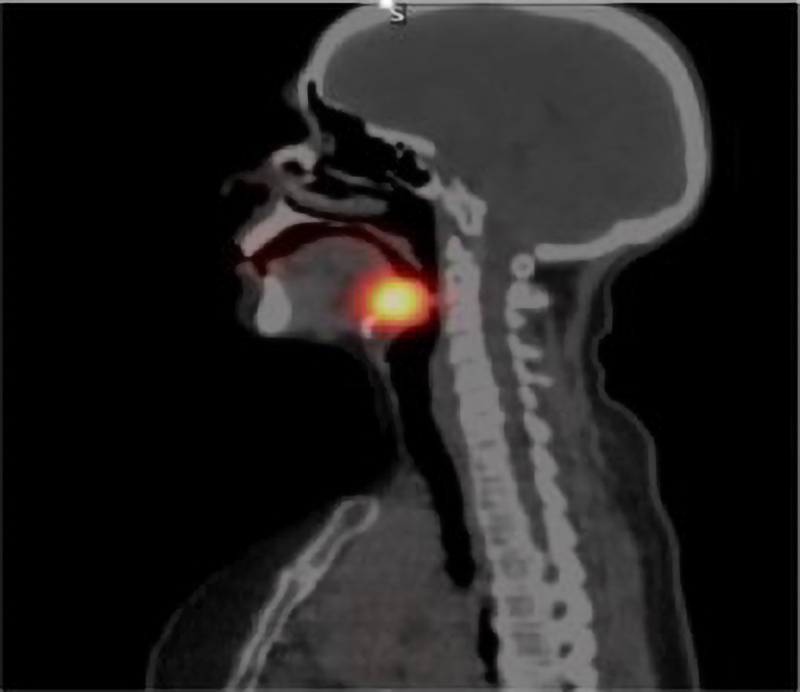

Figure 3.

Technetium (Tc99m) pertechnetate thyroid scintigraphy (TS): Intense activity accumulation at midline due to ectopic thyroid tissue at the base of tongue (Lateral).